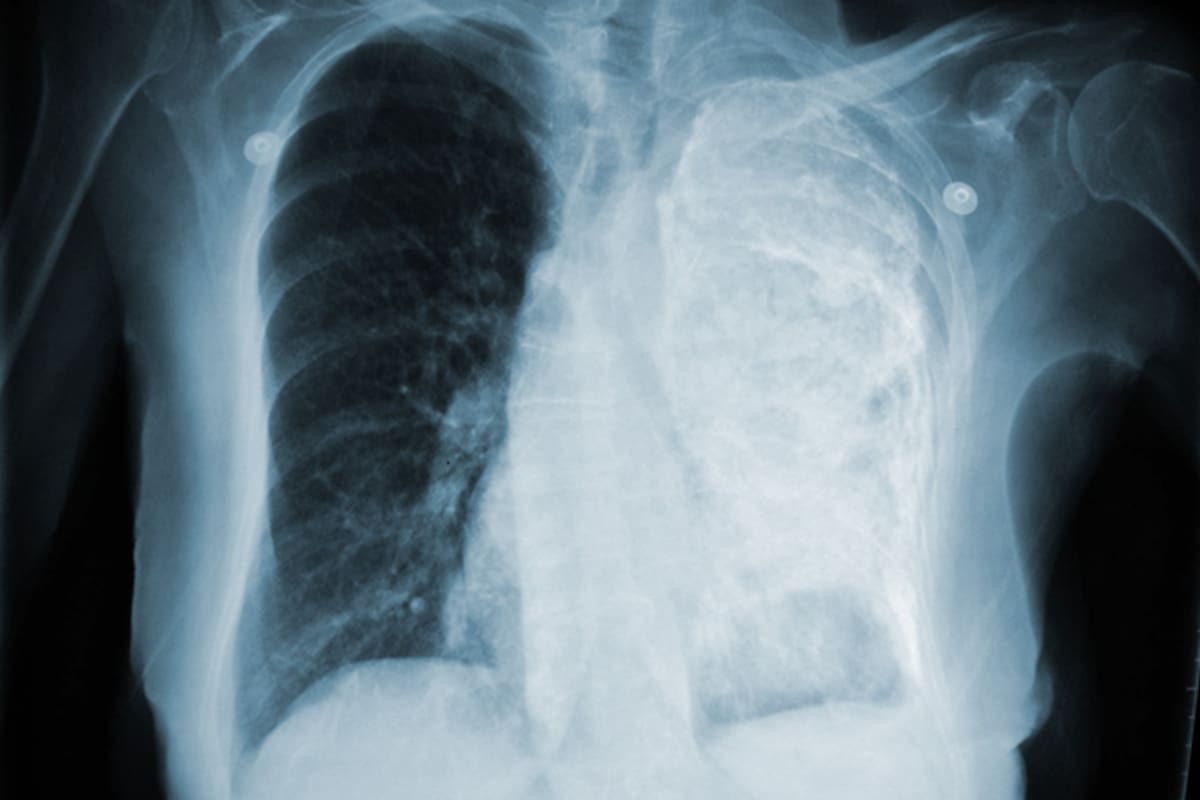

Ven a más jóvenes con daño pulmonar

Detectan a personas hasta de 25 años con cáncer en pulmón a causa del tabaquismo.

Mexicali, B.C.- El principal rango de edad en las que se detecta el cáncer de pulmón es en personas de 60 a 70 años.

Sin embargo, cada vez se ven más pacientes jóvenes, desde 50 años inclusive desde los 30 años, advirtió Larissa Sáinz Núñez, especialista en neumología del Instituto Mexicano del Seguro Social.

“No trato de ser alarmista, pero hemos visto que cada vez son más jóvenes, hemos tenido pacientes desafortunadamente de 30 años, de 25 años, que tienen cáncer de pulmón”.